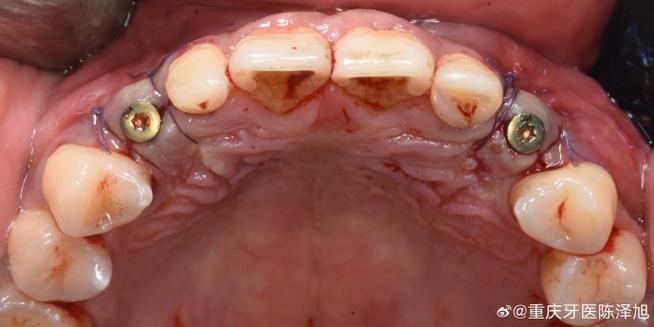

种植体基台的白色革命:传统种植体基台多为钛合金材质,银灰色可能透过牙龈,导致前牙区出现“灰线”,影响美观,氧化锆白色基台成为前牙修复的首选,其乳白色与牙龈颜色自然融合,避免透灰风险,同时强度足够,长期使用不易崩裂。

(图片来源网络,侵删) -